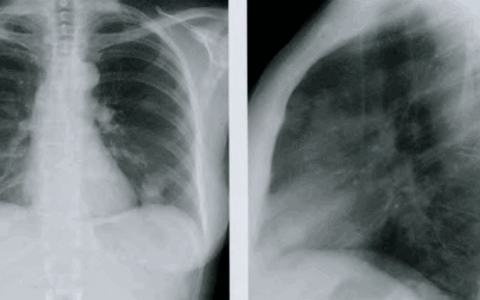

Первичный туберкулезный фокус – это очаг первичного

экссудативно-десквамационного воспаления, затрагивающего несколько ацинусов. Туберкулезная пневмония на ранней стадии характеризуется небольшим очагом с перифокальным неспецифическим воспалением. Затемнение сопровождается расширением корня легкого за счет усиленных бронхолегочных лимфоузлов. Первичный инфильтративный очаг характеризуется биполярными изменениями, при которых инфильтрации затрагивает железистый и легочной компоненты. При неосложненном течении выделяют 4 фазы туберкулеза легких: 1. Пневмоническая – расширение корня с деформацией рисунка, потерей структуры; 2. Рассасывание; 3. Уплотнение – через 2 года; 4. Окостенение и обызвествление первичных очагов (через 5 лет). Усиление прикорневого легочного рисунка при инфильтративном туберкулезном процессе сопровождается выходом артерии за границы плащевидной зоны. В норме мелкие легочные сосуды заканчиваются не менее, чем за 1 см до наружной границы тени легочных полей на рентгенограмме.